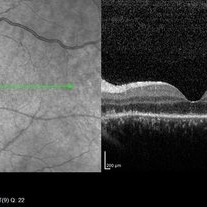

26 year-old male, reports seeing a red dot with his left eye after staring at a projector light. BCVA 0.7 logMar.

Photographer: Dr. Waldemar Godoy, Clínica Godoy. Jalapa, Guatemala.

Imaging device: OPTOPOL SD-OCT

Condition/keywords: subhyaloid blood, subhyaloid hemorrhage